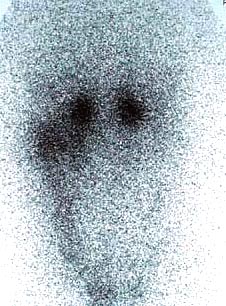

CaseYW01

- Age/Sex: 50M

- Chief Complaint: 頭痛,発汗過多,動悸,体重減少

- Clinical

Course: アルコール性肝炎にて経過観察中。最近1年間、高血圧症の診断で降圧薬を内服している。

- Lab. Data: 末梢血中濃度 Epinephrine 43 pg/ml (基準値 0-80),

Norepinephrine 31400 pg/ml (基準値 90-420), Dopamine 122 pg/ml

(基準値 0-30)

- Images:

- X-CT

- 131I MIBG,

48h

123I

MIBG, 24h

123I

MIBG, 24h

あなたの診断は What

is your first impression?

123I

MIBG, 24h

123I

MIBG, 24h